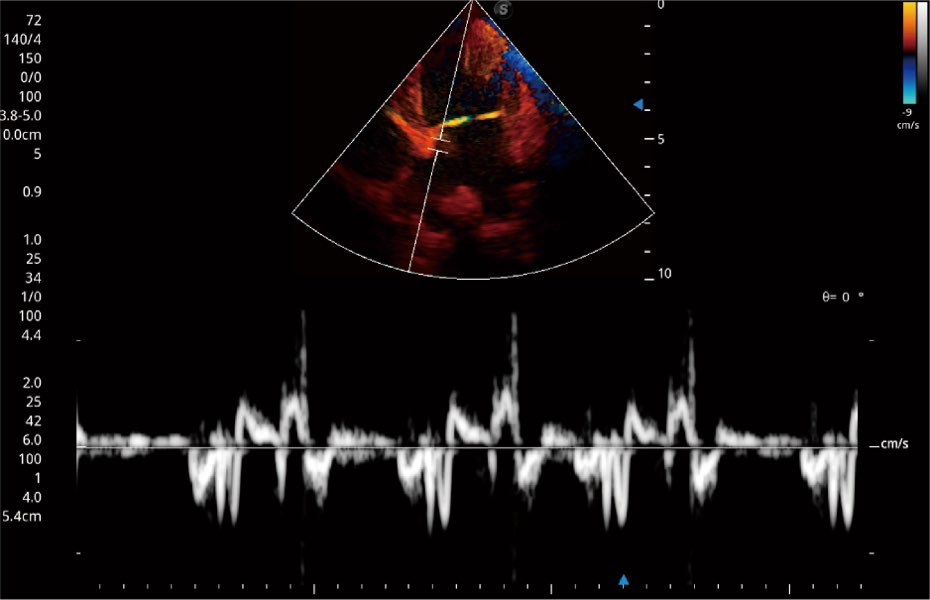

Przy pracach nad aparatem ProPet 60 uwzględniono najważniejsze preferencje i potrzeby weterynarzy, oferując finalnie przystępne cenowo i odpowiednio wyważone połączenie znakomitej precyzji klinicznej, zwiększonej wydajności i przemyślanego przebiegu pracy, niezastąpione w codziennej praktyce weterynaryjnej. Dzięki dostępowi do pełnej gamy głowic HD rozwiązanie to spełnia wszystkie potrzeby w zakresie obrazowania, umożliwiając wykonywanie badań jamy brzusznej, małych narządów, ortopedycznych, badań podczas rozrodu, a nawet badań serca i klatki piersiowej, a to wszystko przy doskonałym stosunku jakości do ceny.